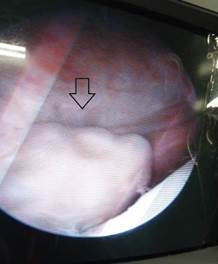

La presencia del CLA en las escotaduras medial (Figura 1) o lateral (Figura 2) son la localización más frecuente de los CLA de pequeño a mediano tamaño, de ahí, la necesidad de palpar con el dedo desde la piel estas áreas para poder mover esta estructura y poder visualizarla. En caso de localización en la escotadura intercondílea, estos pueden quedar atrapados en esta zona o pasar a los compartimentos posteriores en especial el medial.30,31

En caso de realizar el examen artroscópico y no detectar el CLA, se recomienda alargar la incisión suprapatelar e introducir un dedo enguantado del cirujano y continuar la búsqueda. En este momento se debe tener en cuenta que pueden existir repliegues de la sinovial que pueden simular el CLA. Si después de esta maniobra aún no se encuentra el CLA, se recomienda apoyarse en algún examen imagenológico disponible en el salón de operaciones.12,32

Una vez identificado el CLA se procede a atraparlo. Se debe detener la irrigación para impedir su movimiento en todo lo posible. Cuando se localiza en la bolsa suprapatelar, se hace compresión con los dedos pulgar e índice sobre las escotaduras medial y lateral para impedir su descenso; es entonces que se realiza la fijación del CLA mediante una aguja, preferiblemente por las partes blandas del CLA. En caso de estar localizado en las escotaduras, se debe hacer la fijación igual con aguja de forma percutánea.12,30